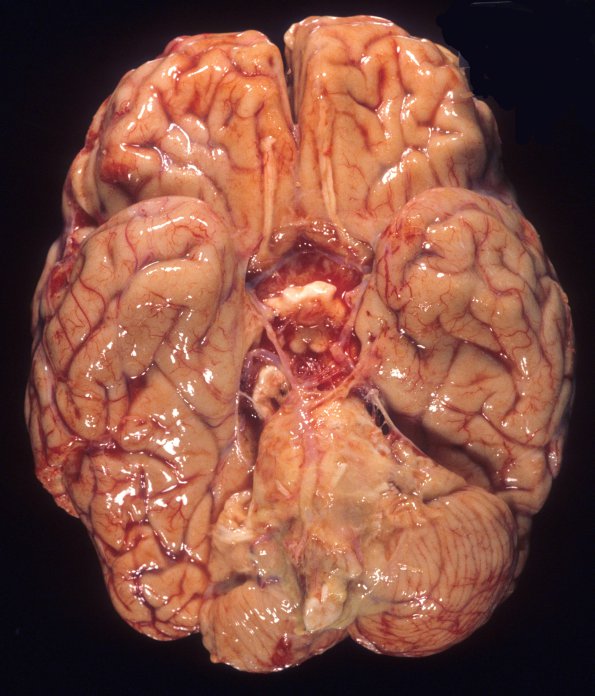

The base of the brain shows prominent opacification of the leptomeninges by purulent exudate in this patient with streptococcal meningitis.